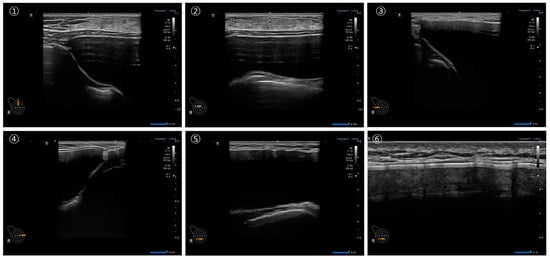

A minimum of six sonographic images and videos were captured for each breast, ensuring comprehensive information for a thorough assessment of individual breast implants, as illustrated in Figure 4. In Figure 4A, each number indicates the optimal location for specific information: (1) optimal position to check the breast implant pocket, (2) checkpoint for the upper part of the breast implant and periprosthetic space, (3) checkpoint for the lateral part of the breast implant and periprosthetic space, (4) checkpoint for the medial part of the breast implant and the periprosthetic space, (5) checkpoint for the inferior part of the breast implant and the periprosthetic space, and (6) optimal position for identifying the breast implant shell surface topography.

Figure 4B illustrates the optimal locations for specific video information, guiding the probe downward or horizontally toward the red arrow. Each number corresponds to assessing distinct aspects: (1) the lateral part of the breast implant and periprosthetic space, (2) the central part of the breast implant and the periprosthetic space, (3) the medial part of the breast implant and the periprosthetic space, (4) the upper part of the breast implant and the periprosthetic space, (5) the lower part of the breast implant and the periprosthetic space, and (6) the shell surface topography of the breast implant. Examples of ultrasonographic images strategically positioned for the optimal assessment of breast implant integrity are depicted in Figure 5.

Figure 5. Examples of breast implant ultrasonography. ① US image of the lateral part of the breast implant and periprosthetic space, ② US image of the central part of the breast implant and the periprosthetic space, ③ US image of the medial part of the breast implant and the periprosthetic space, ④ US image of the upper part of the breast implant and the periprosthetic space, ⑤ US image of the lower part of the breast implant and the periprosthetic space, and ⑥ US image of the shell surface topography of the breast implant.